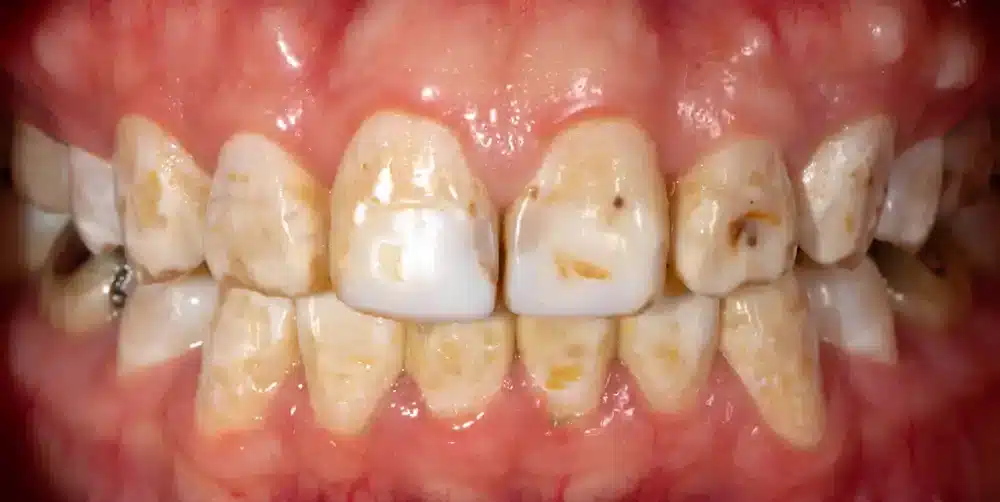

- ระดับปานกลาง (Moderate Fluorosis) – รอยสีขาวสังเกตเห็นได้อย่างชัดเจน อาจเริ่มมีรอยสีคล้ำมากขึ้น ผิวฟันเกิดความสึกกร่อน และหยาบ โดยกระทบต่อผิวฟันประมาณ 25-50%

- ระดับรุนแรง (Severe Fluorosis) – มีรอยคล้ำ กระดำกระด่าง บนผิวฟัน มักมีสีดำ หรือน้ำตาล เคลือบฟันเกิดความเสียหายอย่างชัดเจน และรุนแรง